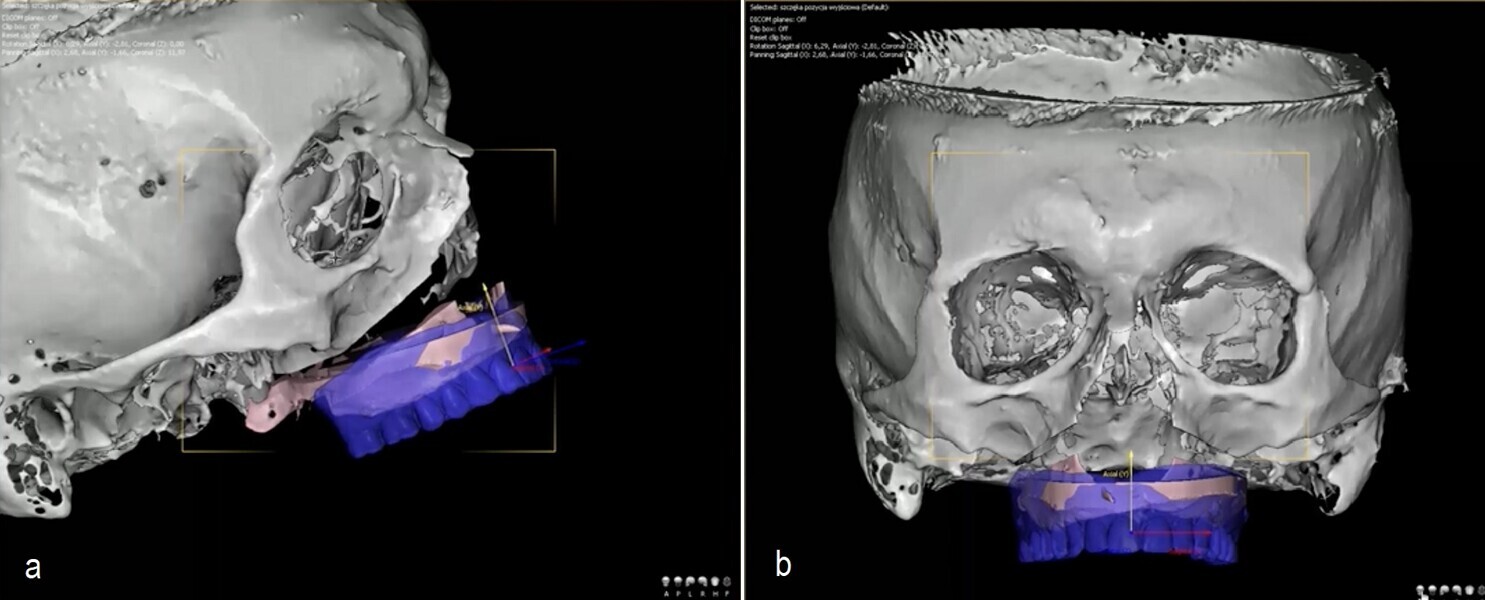

During surgery, I use two 3D-printed surgical guides: one affixed before the osteotomy to guide implant and anchor pin positioning, and the second used after repositioning the maxilla to confirm implant alignment and skeletal placement. This workflow enhances reproducibility and reduces human error, the only variable being the quality of diagnostic data.

I recently applied this technique in the treatment of a 69-year-old patient with longstanding edentulism and advanced maxillary bone loss. The procedure, planned entirely with DDS-Pro, allowed for accurate implant placement and maxillary repositioning (Figs. 1–4). Carried out under general anaesthesia, the surgery took approximately 2 hours and was completed without complication (Figs. 5 & 6). The surgical guides functioned exactly as expected, leading to a stress-free operation.